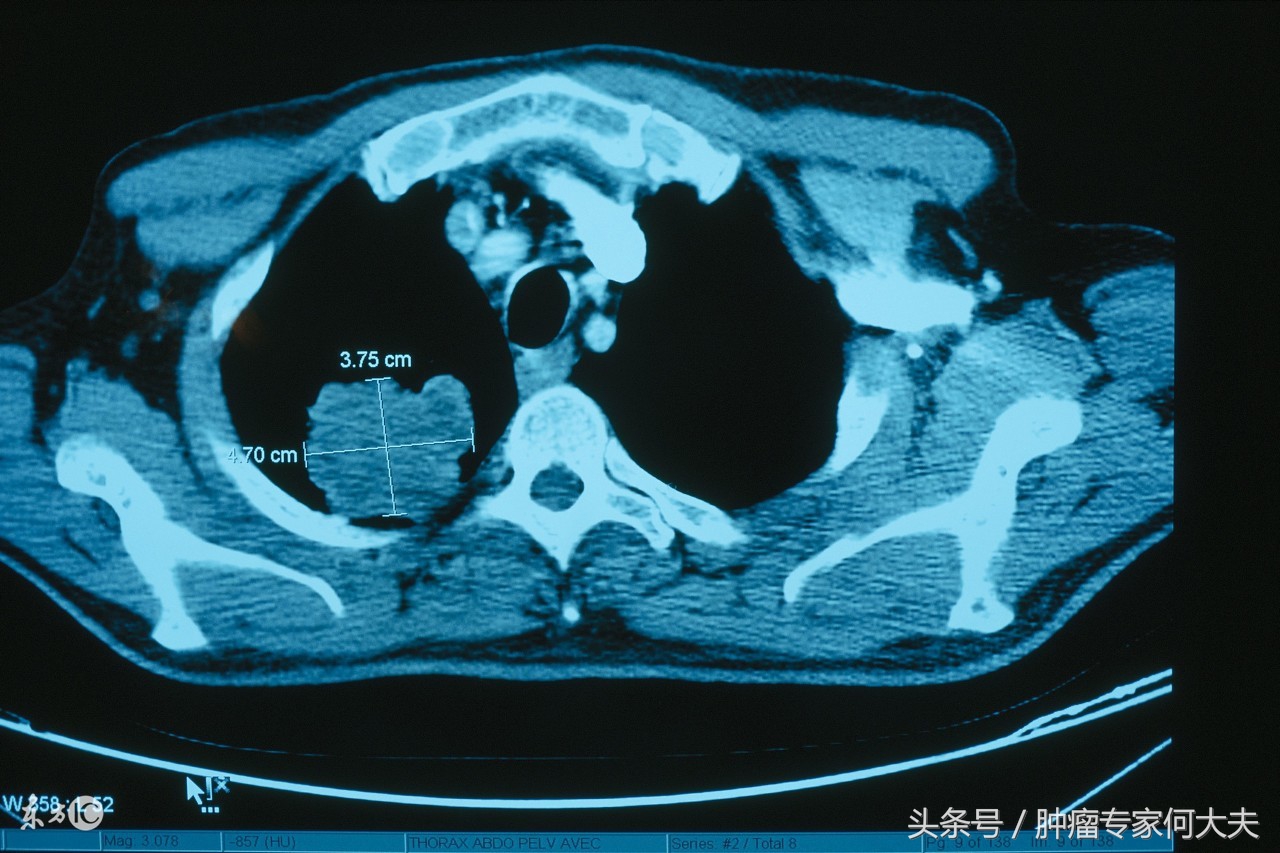

右肺癌

王先生,今年57岁,辽宁省葫芦岛市人,12年前因为咳嗽在当地医院呼吸科诊断为变异性哮喘,医生给予激素、支气管舒张剂等药物治疗,很快就能缓解,但每年逢秋冬季节,都得犯一次病,有时候一年犯两到三次,每次犯病医生给的药都很给力,由于成了“*毛老**病”,所以王先生自己以及他的医生都有惯性思维了,但就在2015年11月初,王先生再次“犯病”了,他的医生对他的病很熟悉,仍然按照“*毛老**病”处理,可这次处理完他缓解不明显,咳嗽很剧烈,为刺激性干咳,夜里入睡都成问题。持续了将近3周,医生建议他查胸部CT看看,结果让王先生和他的医生惊呆了,“右肺占位性病变,伴两肺多发小结节影,多发纵膈淋巴结肿大,考虑淋巴结转移,建议进一步检查”。经过气管镜和全身PET-CT检查,诊断为右肺鳞癌,IV期。确诊肺癌晚期的王先生,非常绝望,对他的医生也非常不满,后来一度将多年为他诊病的医生告上了法庭,但法庭认为王先生患有明确的“变异性哮喘”旧病,医生第一时间的处理按照经验性治疗不构成医疗差错和漏诊,后来这事就不了了之了。